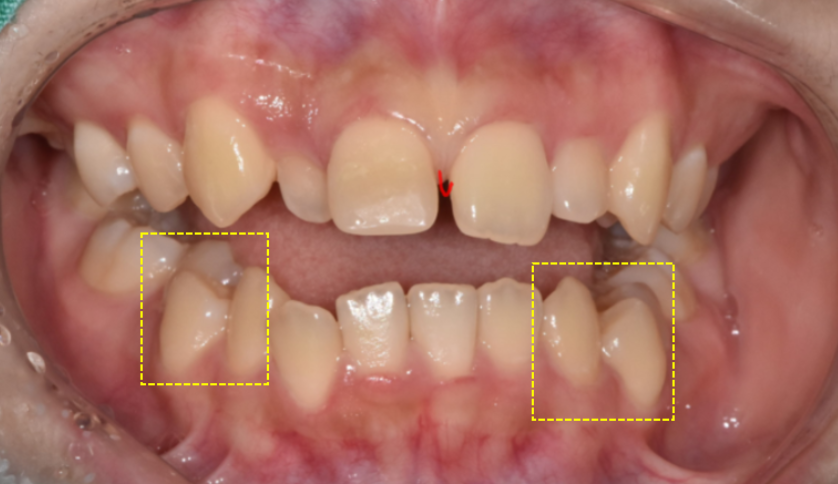

오늘 환자분도 왜소치로 내원을 해주셨는데

치아 배열이 전체적으로 교정이 필요했습니다.

교정과 보철 치료

각각 역할 분담이 필요한데요.

교정을 통해 전체 치열을 가지런하게 정리하여

보철 치료가 들어갈 수 있는 기초 작업을 완성해야합니다.

교정으로 공간이 만들어지면

그때 왜소치 크기를 정상치와 비슷하게 맞추어 줍니다.